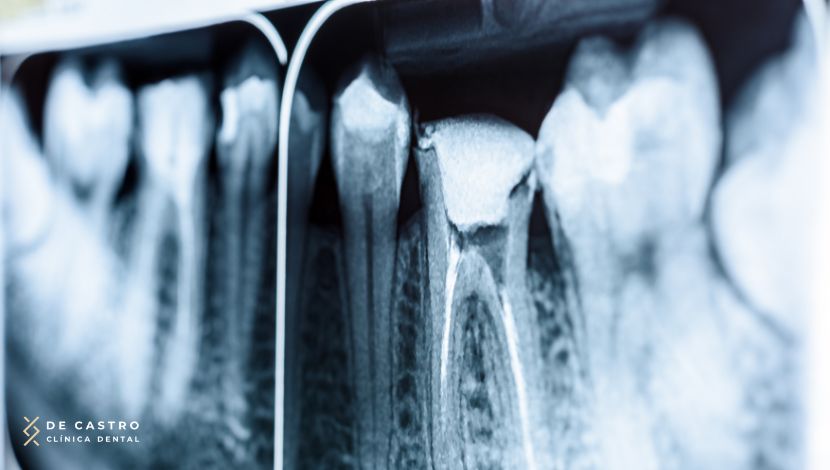

Lo primero es valorar el estado del diente con una exploración y una radiografía. Así confirmamos si la pulpa está dañada o infectada, y planificamos cómo será el tratamiento.

A veces también realizamos pruebas de sensibilidad o percusión.